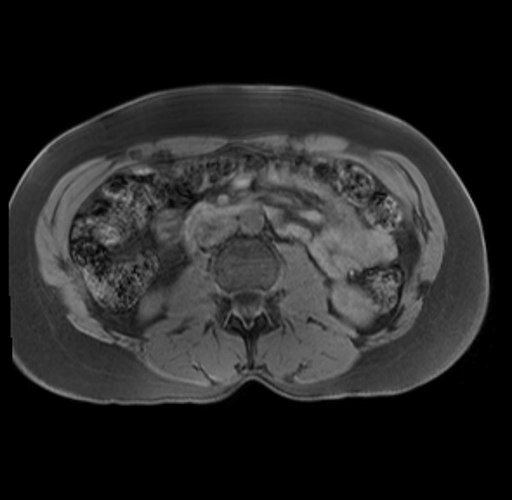

Imaging Analysis

Look through the patient's CT scan to identify any areas of concern for the necessary procedure.

Based on your CT findings, which issue(s) are present and would give reason for "planned slowing down moment(s)" in this case?